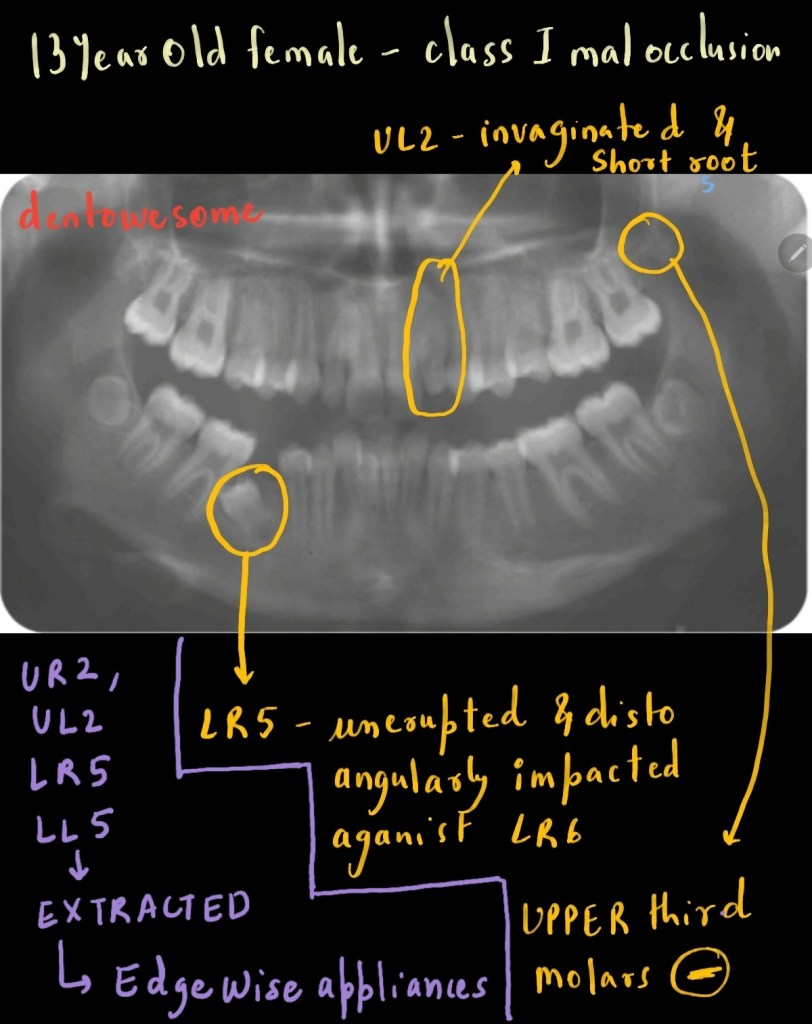

A 13-year-old female presented with a class I malocclusion on a mild skeletal class II pattern with average vertical dimensions complicated by impaction of the LR5 and an invaginated UL2

What is treatment plan? Which tooth will be extracted? What factors need to be considered when substituting a maxillary canine for a lateral incisor?